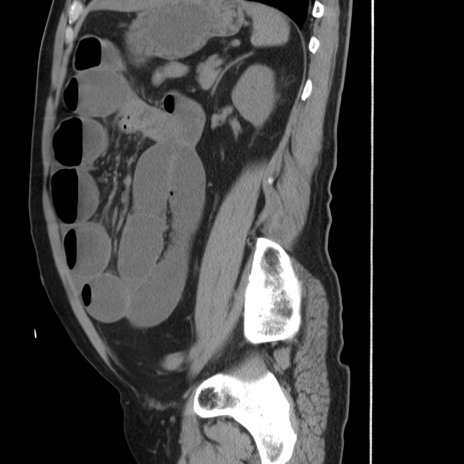

冠状断像

【症例】 60歳代男性

【主訴】 腹部膨満、嘔吐

【現病歴】5日前頃より倦怠感を認め食事量減少し4日前の朝嘔吐、食事摂取困難となった。 3日前近医受診し点滴施行され整腸剤などを処方された。 当日他院を受診し、腹部膨満著明、炎症反応の上昇(CRP10.8、WBC11200)あり、紹介受診となる。

【身体所見】 意識JCS1 受け答えがはっきりしないBP 111/57mHg、 P 67bpm、、BT35.2°C、SpO2 97%(RA)、 腹部:膨隆、打診で鼓音あり、全体的に圧痛有り、腸蠕動音(-)、反跳痛ははっきりせず。

【データ】WBC 11400、CRP 14.20